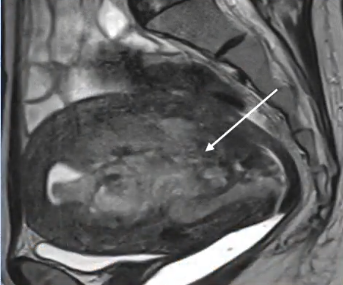

![]() |

| 矢状位 T2 加权磁共振成像 菜花型子宫内膜肿块 | |

| 轴位 T1 增强扫描显示 病变的低强化* | 冠状位 T2 加权磁共振成像 菜花型子宫内膜肿块 |